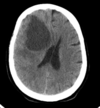

Qual a densidade do sangue fresco na TC?

hiperdenso

(imagem = TC de área hiperdensa com efeito de massa - hematoma frontal e recente)

Quais os achados radiológicos?

Qual a principal hipótese diagnóstica?

herniação subfalcina, lesão hipodensa em lobo frontal e parietal direitos, efeito de massa sobre o ventrículo direito com desvio da linha média à esquerda